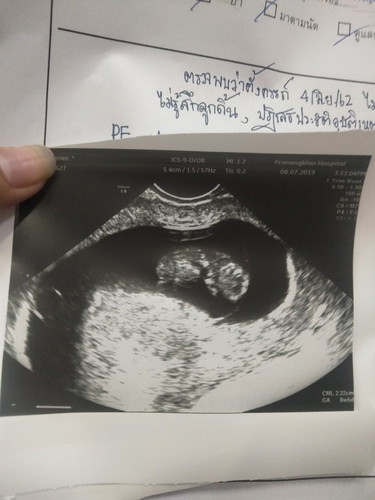

17วีค

ขอบคุณสำหรับที่ได้เข้ามาในเเอปคุณเเม่น่ะค่ะวันนี้น้องหัวใจไม่เต้นเเล้วต้องนำน้องออกโดยสอดยา#เกิดมาเป็นลูกเเม่ใหม่น่ะลูก?